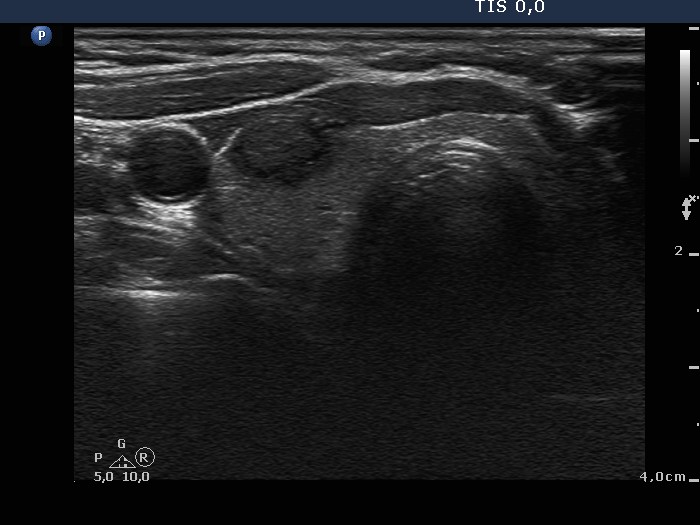

The borders of the nodule - case 638 |

Clinical presentation: A 68-year-old woman was referred for evaluation of a nodule discovered on neck ultrasonography. She was treated for breast cancer, which gave metastasis to the lung.

Ultrasonography. There was a hypoechogenic nodule with cotton-like hyperechogenic patches and smaller punctate hyperechogenic granules in the right lobe. The nodule presented intranodular blood flow and lobulated margins.

Cytological diagnosis: suspicion of medullary carcinoma.

Histopathology: medullary carcinoma

Comment. The tumor presents lobulated margins.